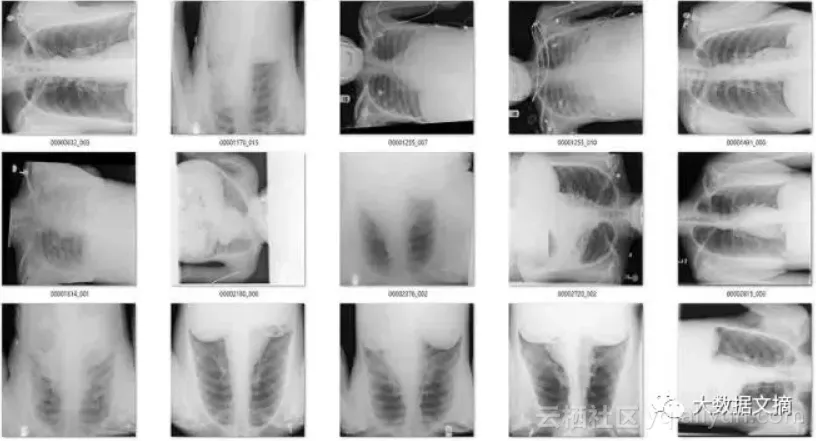

在余下的120个图像中,56个并不是正面胸片。其中主要包括了侧面胸片和腹部X光片,这也是我想要清理出去的异常图片。

那么其余的呢?有一些是经过混合的缩小图像(它们有着黑色或白色的大边界),因为过度曝光而变淡的图像(其中有一些图像整体都是灰色的),还有像素颜色完全翻转的图像等等。

即使是很少量的带标签的数据都很有帮助。我用旋转检测器检测到的侧面和错误区域的X光图(n=56张)训练了一个新的模型。

结果很好!新的模型帮我找到了几百张侧面,腹部和骨盆X光图。